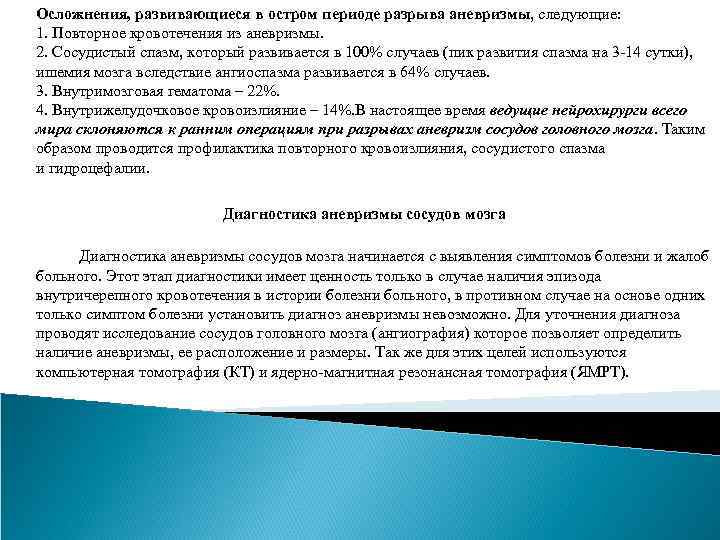

Каротидная ангиограмма больного с гигантской аневризмой 3 D-KT ангиограмма больного с аневризмой средней мозговой артерией